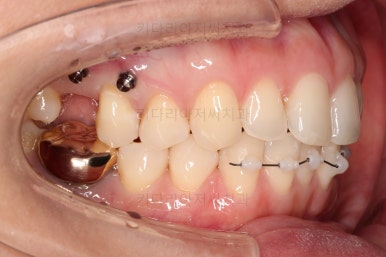

어금니가 문제였습니다.

윗니 어금니가 하나 없는 상태였고요.

어금니가 없이 지낸지 꽤 시간이 흐른터라 뒤쪽 어금니가 앞으로 쓰러져 공간을 잠식하고 있었습니다.

물론 현재 모습대로 임플란트를 할려면 할 수 있지만 장기적으로 쓰러진 치아를 계속 사용하는게 치아수명에 바람직 하지 않죠.

임플란트도 원래 들어가야 할 어금니의 크기보다 많이 장가서 기능적으로 좋지 못하고요.

어금니쪽은 쓰러진 어금니를 원위치 시키기 위해서 미니스크류를 식립하여 준비작업을 해줍니다.

어금니 위치 조절을 계속 해주고요.

어금니도 원위치로 많이 갔네요.